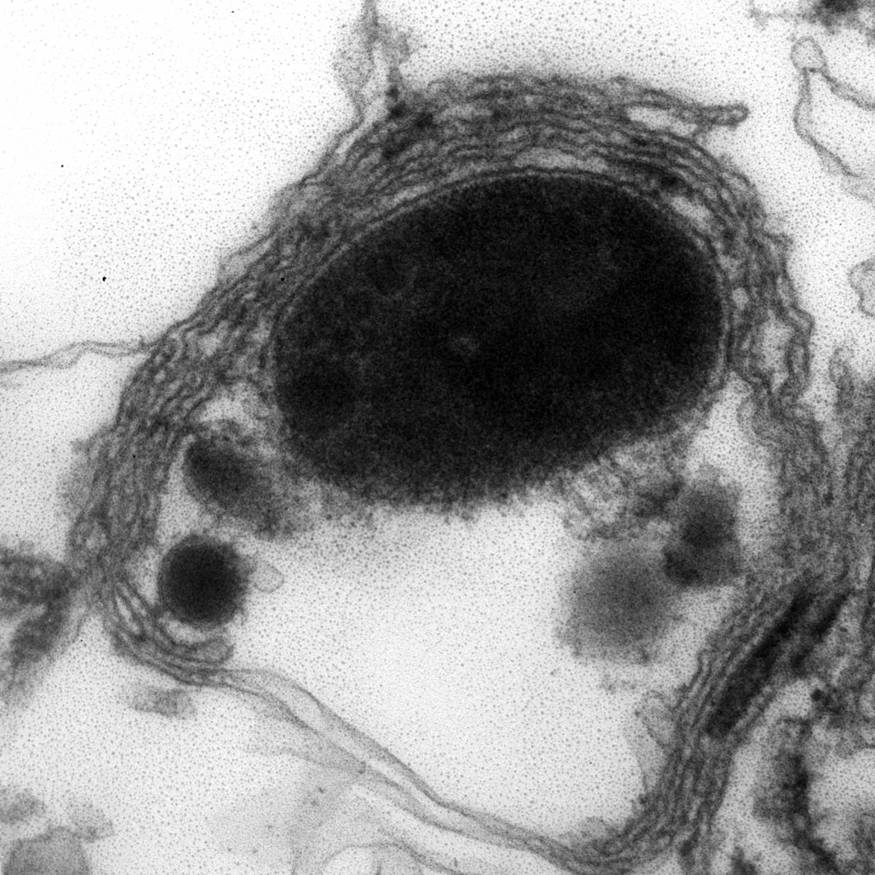

Electron microscopy description

- Abundant intracytoplasmic lipid droplets of varying sizes

- Prominent microvillous projections along cell borders

- Abundant smooth endoplasmic reticulum

- Prominent, round to oval mitochondria; cristae may have tubular to vesicular (zona fasciculata) or lamellar (zona reticularis) profile